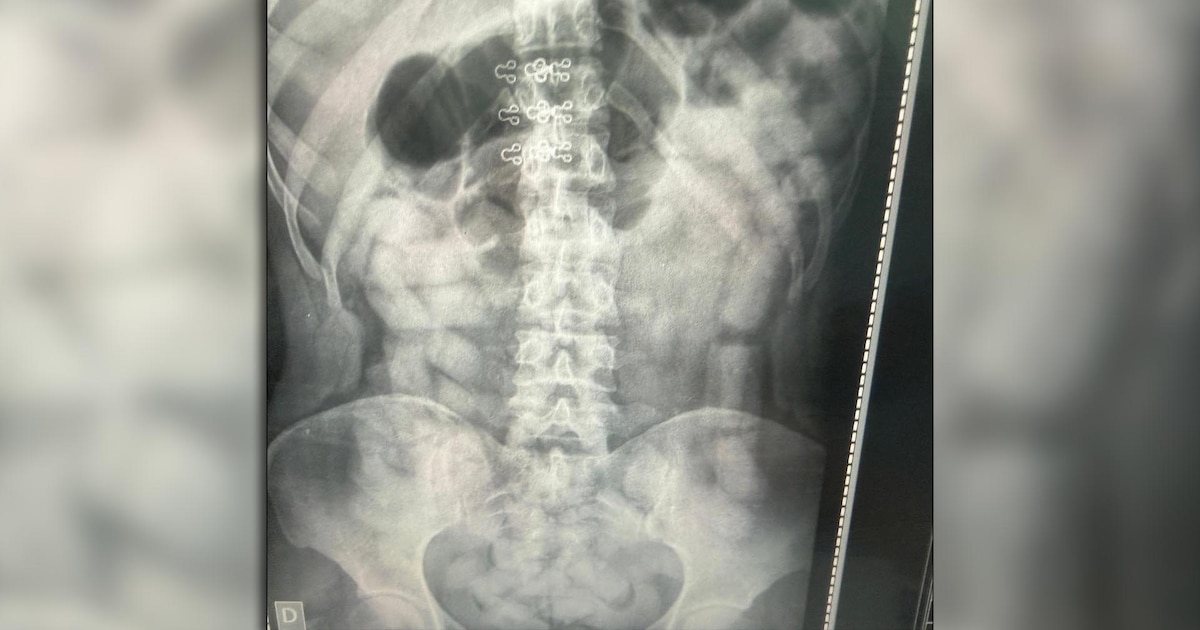

A la mañana siguiente, las sospechas sobre el uso de la modalidad de “mulas” llevaron a que se practicaran placas radiográficas a todos los pasajeros. Las imágenes revelaron cuerpos extraños en el abdomen de cuatro mujeres y dos hombres, una de las placas ilustra este artículo. La modalidad es altamente peligrosa para la salud.

Los seis pasajeros identificados fueron internados bajo custodia en los hospitales de Santa Ana y Los Sarmientos, donde expulsaron un total de 503 cápsulas con un peso superior a los 6 kilos de cocaína . El área de Criminalística y Estudios Forenses contabilizó un total de 752 cápsulas con 10 kilos 316 gramos de la droga.